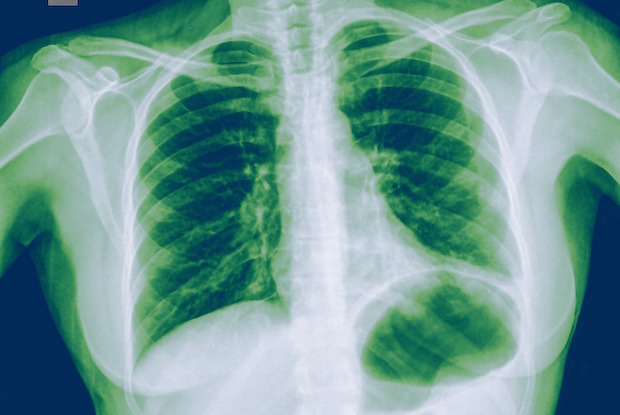

Teraz nastal dôležitý obrat, pretože sú už k dispozícii aj dôkazy vysokej vedeckej sily. Výskumníci wuhanskej univerzitnej nemocnice Zhongnan predbežne publikovali výsledky pilotnej randomizovanej dvojito zaslepenej placebom kontrolovanej štúdie: vitamín C v dávkach 12 gramov, podávaných infúziou 2x denne (t.j. súhrnne 24 g denne) počas 7 dní, spôsobil u kriticky chorých pacientov s COVID-19:

1, súvislé zlepšovanie parametrov okysličenia (PaO2/FiO2),

2, výrazné zníženie zápalového markeru (IL-6),

3, zníženie úmrtnosti o 59%.

Je pritom charakteristické zistenie štúdie z USA, že kritickí pacienti s COVID-19 majú deficitné hladiny vitamínov C a D, pričom najnižšie hladiny mali tí, ktorí nakoniec neprežili.